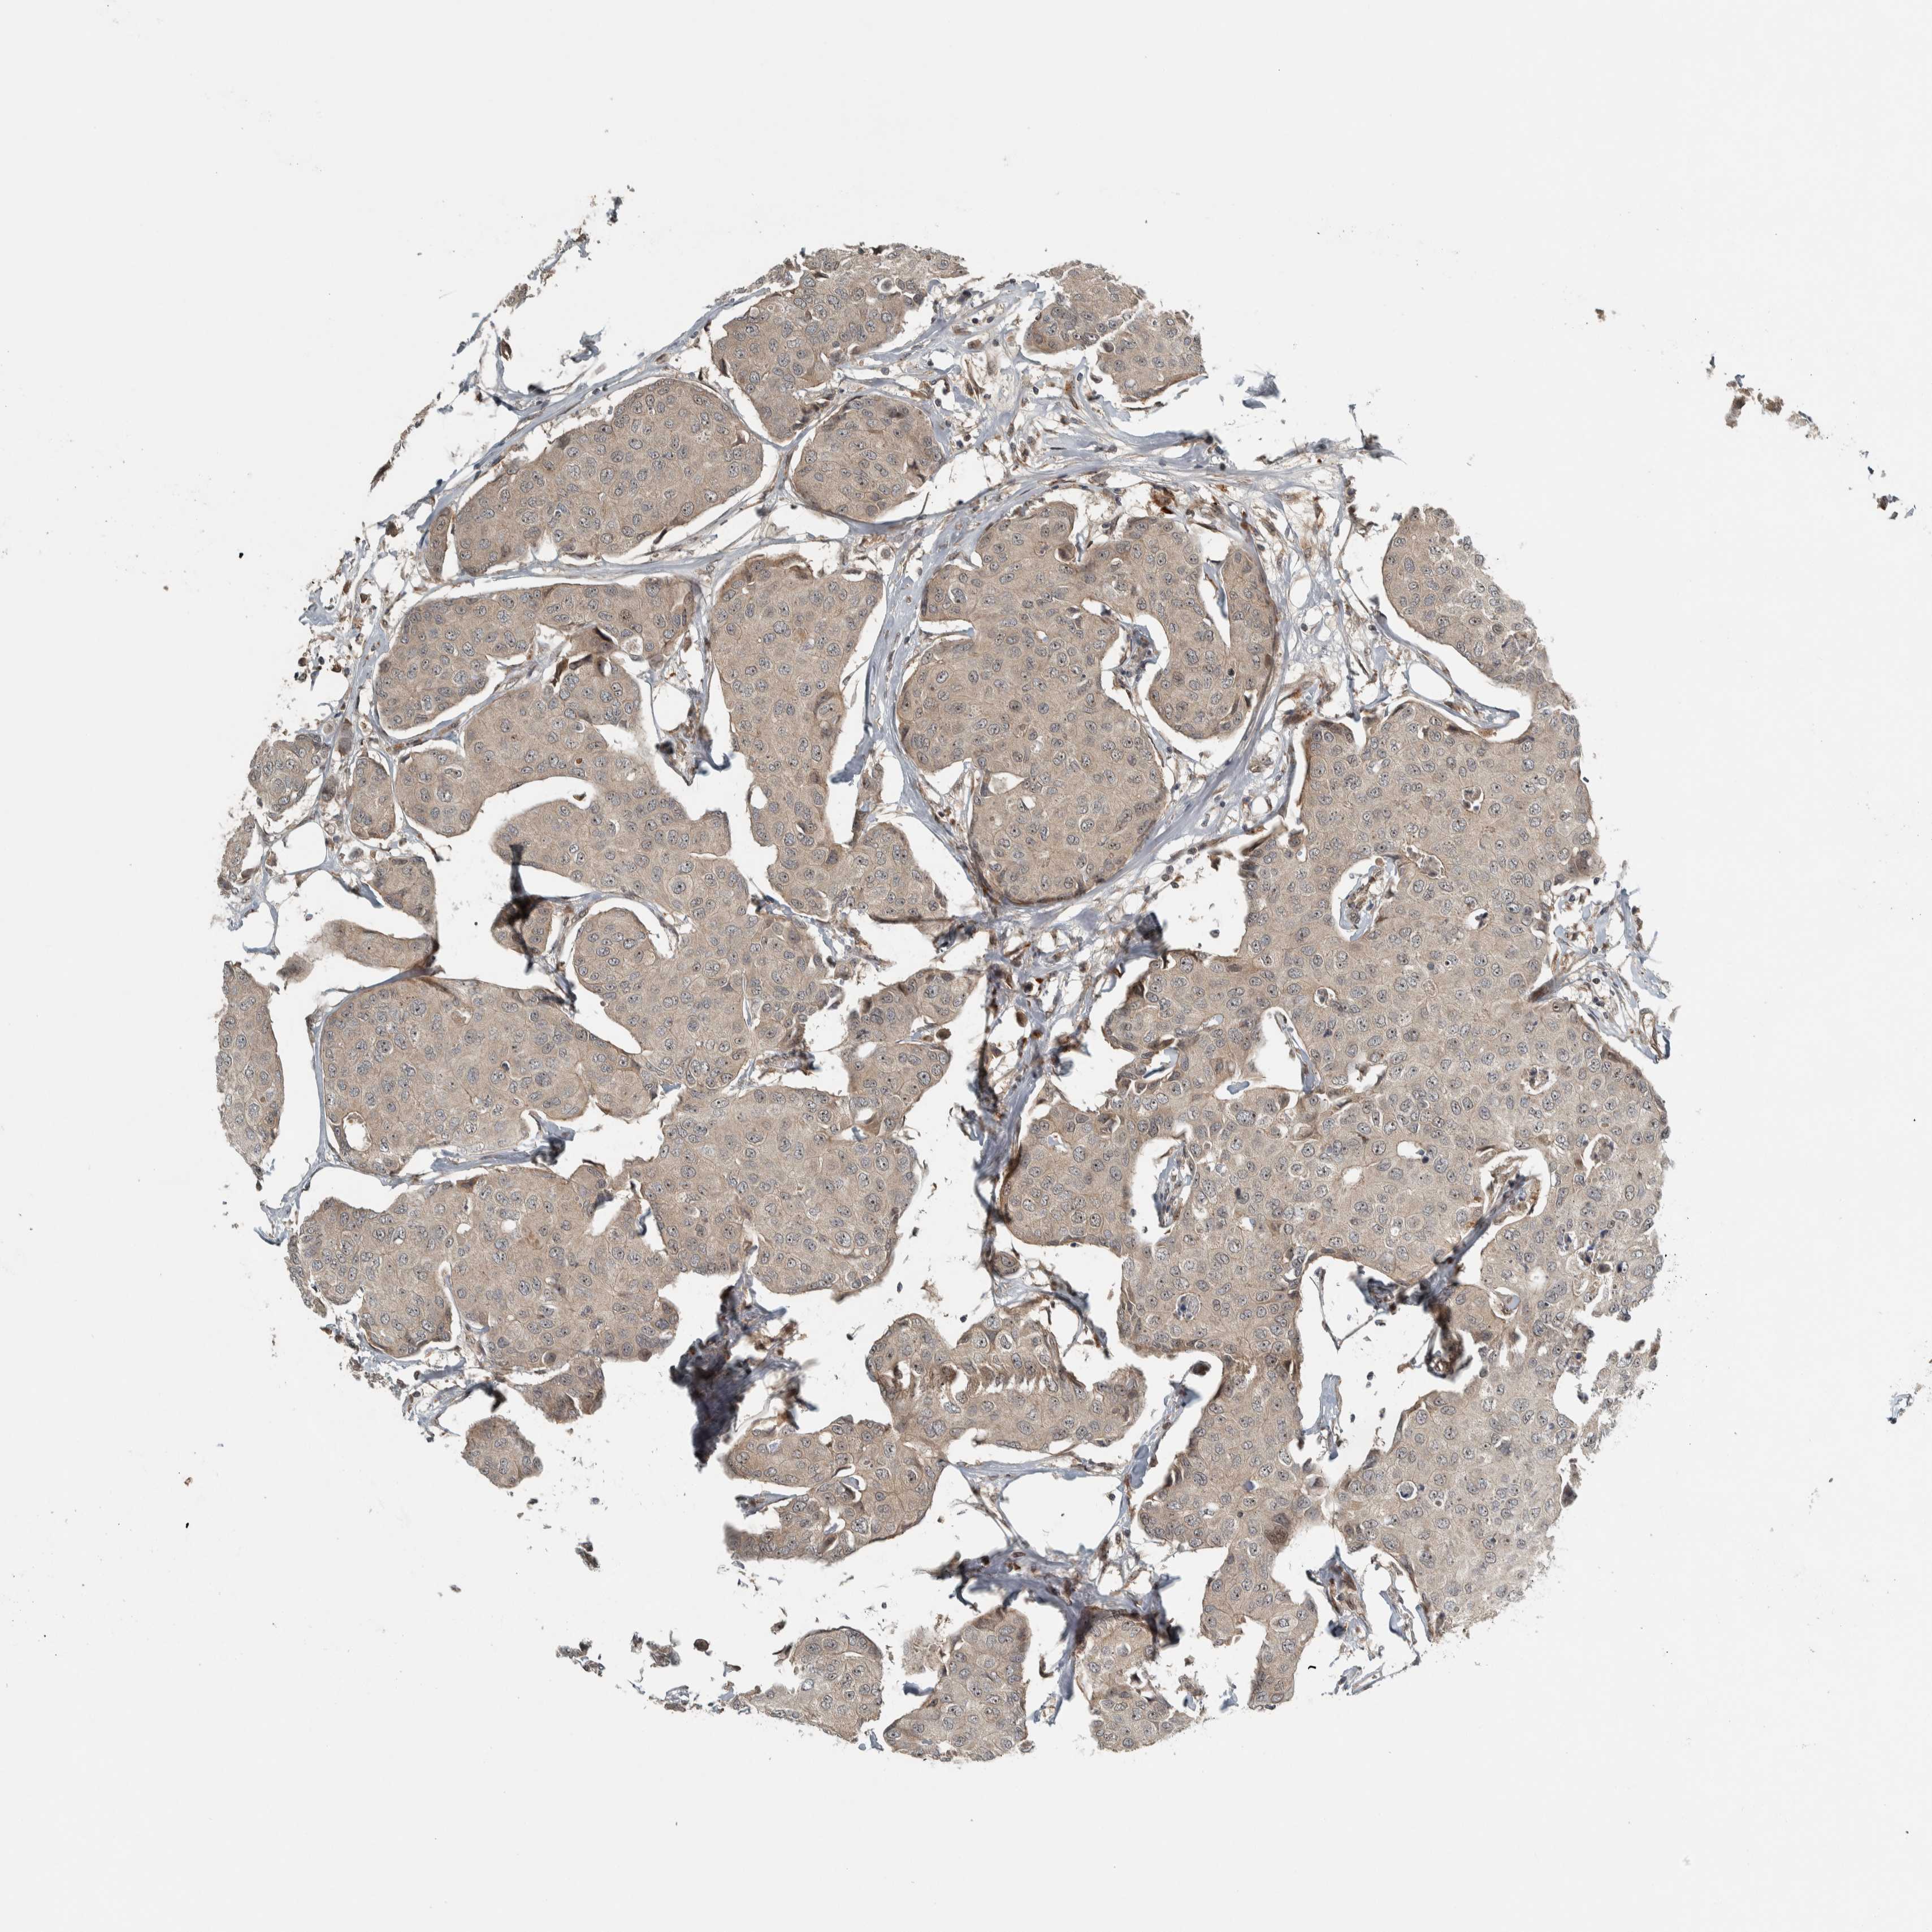

BRCA TCGA BRCA VALIDATION PROTEIN EXPRESSION